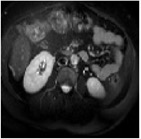

This work presents a novel framework CISFA (Contrastive Image synthesis and Self-supervised Feature Adaptation)that builds on image domain translation and unsupervised feature adaptation for cross-modality biomedical image segmentation. Different from existing works, we use a one-sided generative model and add a weighted patch-wise contrastive loss between sampled patches of the input image and the corresponding synthetic image, which serves as shape constraints. Moreover, we notice that the generated images and input images share similar structural information but are in different modalities. As such, we enforce contrastive losses on the generated images and the input images to train the encoder of a segmentation model to minimize the discrepancy between paired images in the learned embedding space. Compared with existing works that rely on adversarial learning for feature adaptation, such a method enables the encoder to learn domain-independent features in a more explicit way. We extensively evaluate our methods on segmentation tasks containing CT and MRI images for abdominal cavities and whole hearts. Experimental results show that the proposed framework not only outputs synthetic images with less distortion of organ shapes, but also outperforms state-of-the-art domain adaptation methods by a large margin.